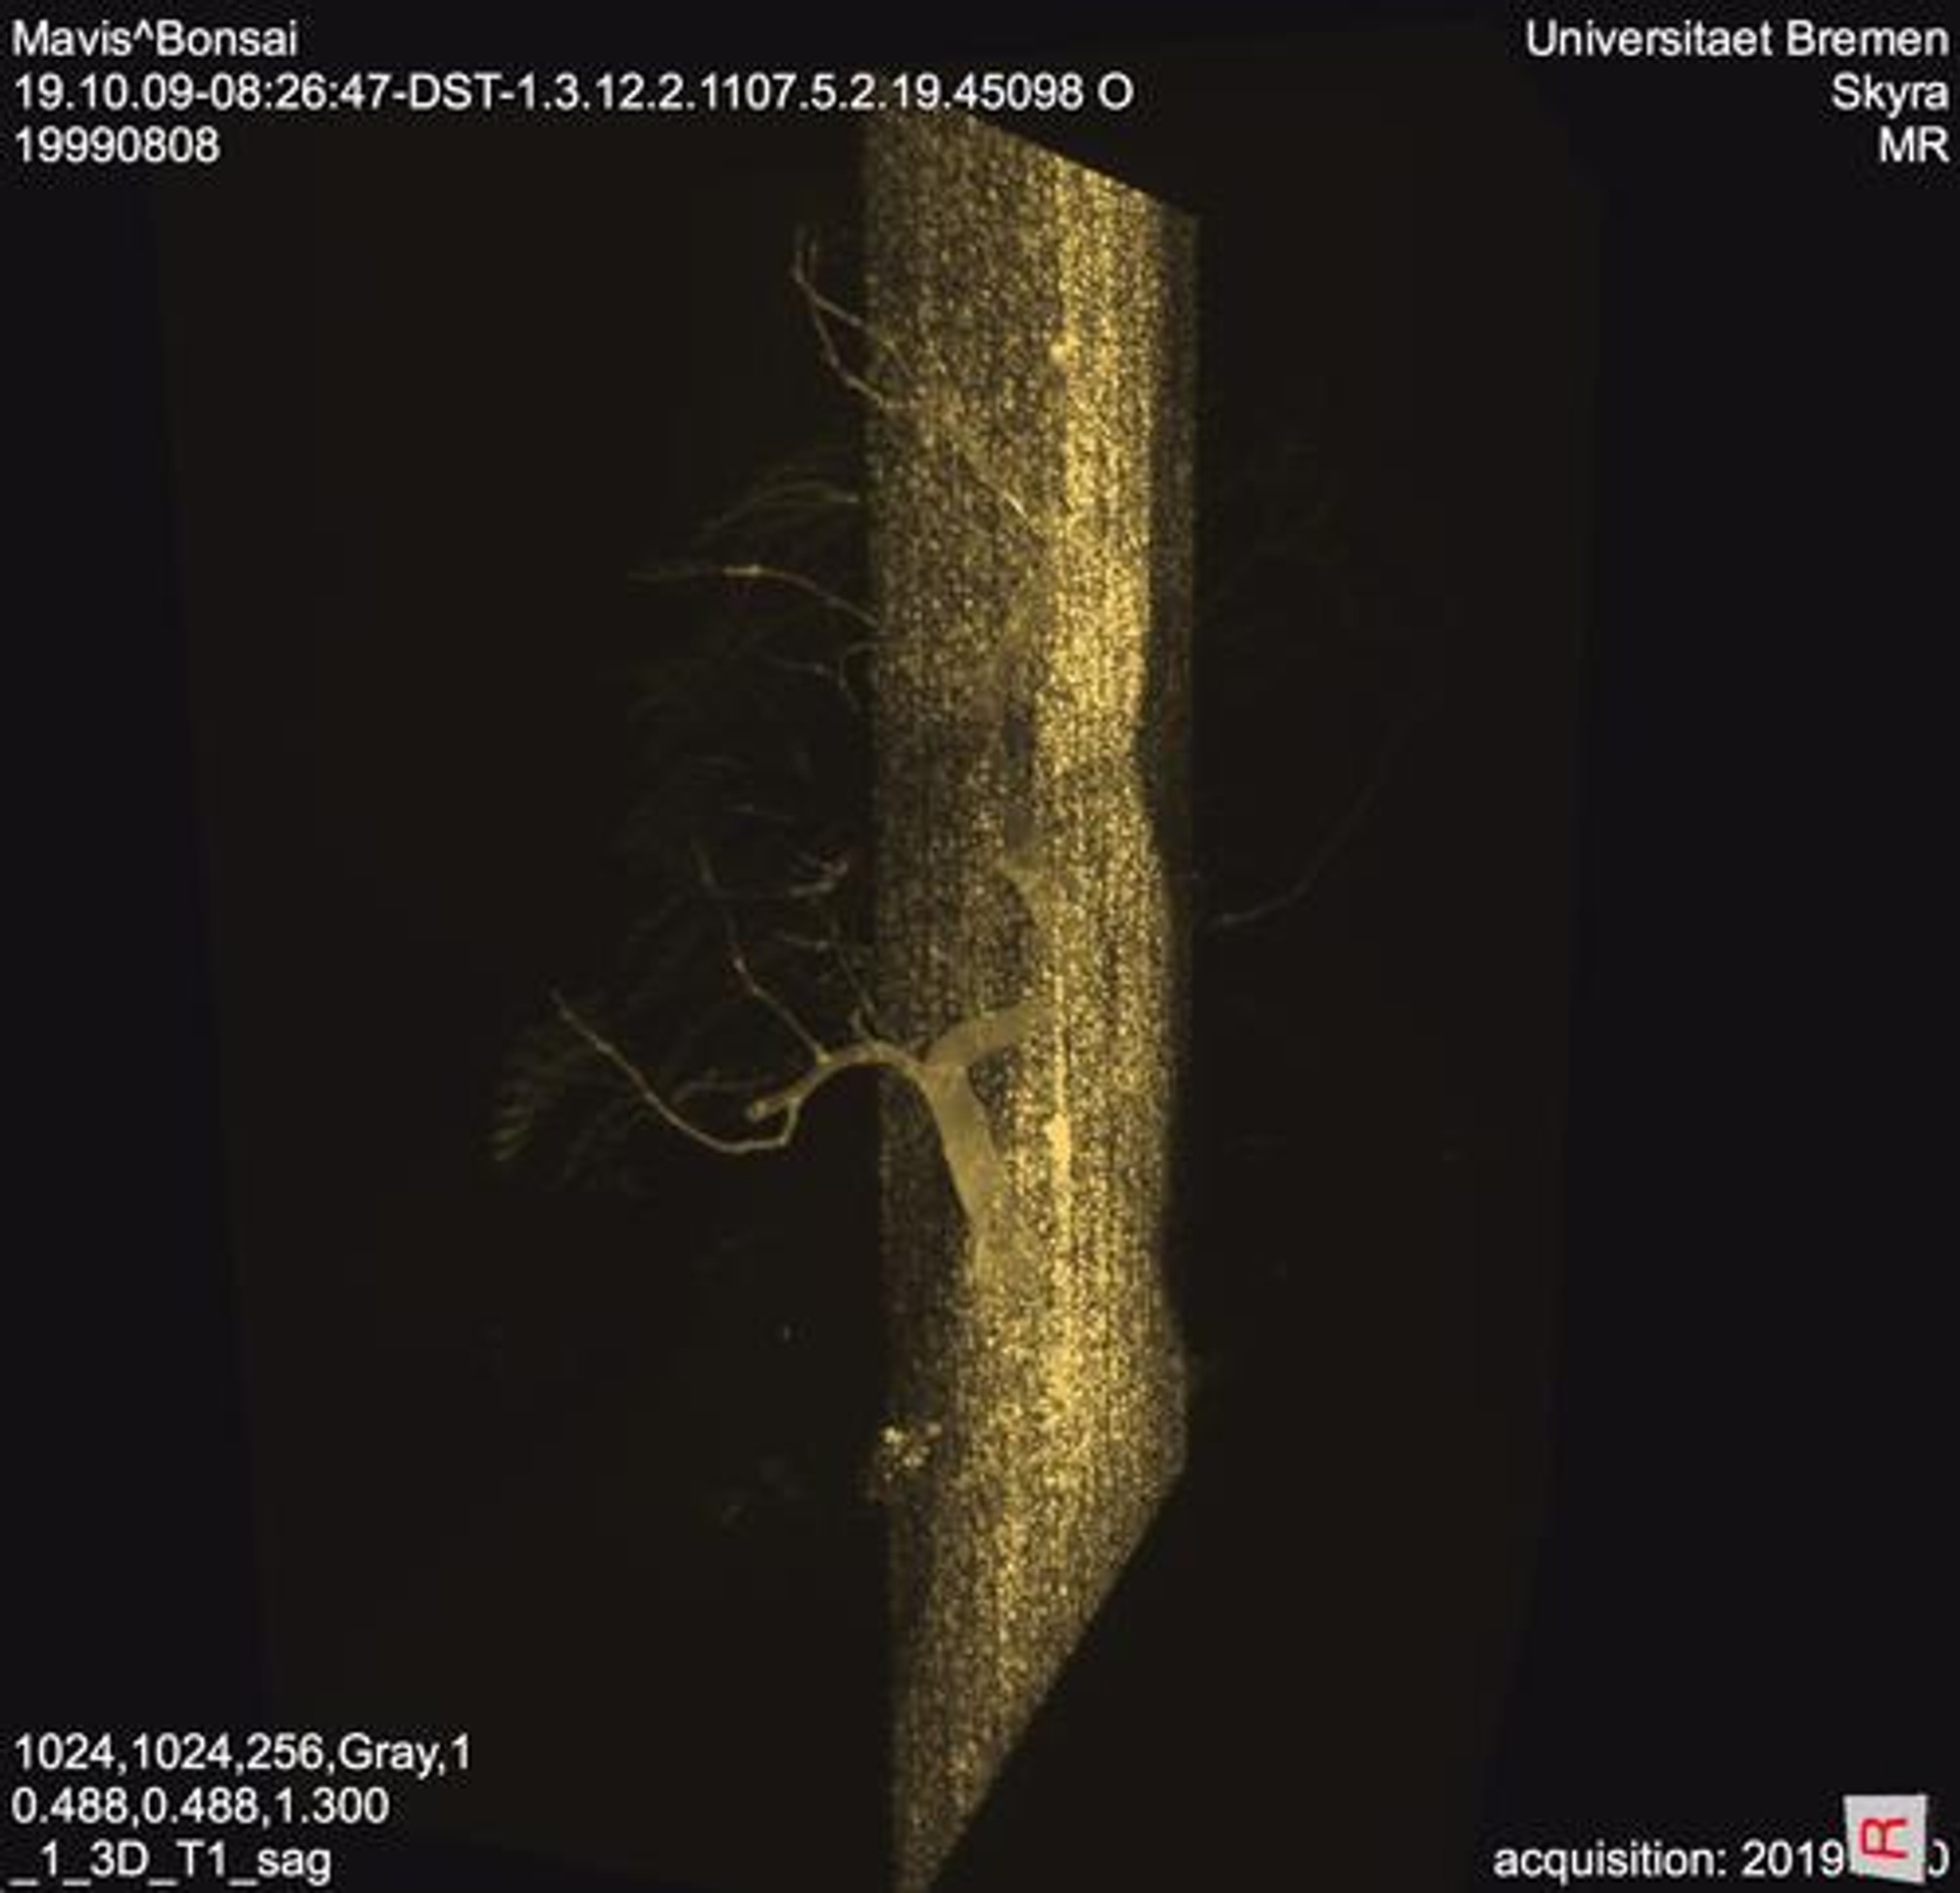

In Vivo is an interactive art science installation that asks the question, what does it mean to be alive? The project is utilising research collected during a six weeks international “STEAM Imaging”¹ residency co-organised and hosted by Institute for Digital Medicine Fraunhofer MEVIS, the International Fraunhofer Talent School Bremen and Ars Electronica. The project is also done in connection with Nanyang Technological University Singapore.² The residency was awarded in June 2019 though an open art call and took place from October - November 2019. The installation integrates sensors and microcomputers and uses the possibilities of the virtual and augmented reality to talk about the relationship between man, machine and nature. The project attempts to shed light on the transitional areas between life and death through the artistic means of photography and video installation. More specifically, the installation tracks the rhythms of the action potential in a bonsai plant and directly affect thousands of MR (magnetic resonance) images captured using an MRI machine. Using projection mapping and soundscapes generated and translated from the MR images, the installation “ gives voice” to the bonsai and give the audience an insight into a living being.

The project is supported by medical visualisation technology, in this case an MRI (magnetic resonance imaging) machine and presents it in an interactive and accessible way for people to visualise the process of the image capturing process. By using MRI, can we find out or can we see what is within the living? Working with

scientists, mathematicians and physicists from the Institutute for Digital Medicine, we have collected thousands of images of the bonsai in an MRI machine. The artists’ request presented a novel challenge for the researchers at MEVIS, who usually work on methods to improve MR imaging of human patients. Imaging plants were new to them.